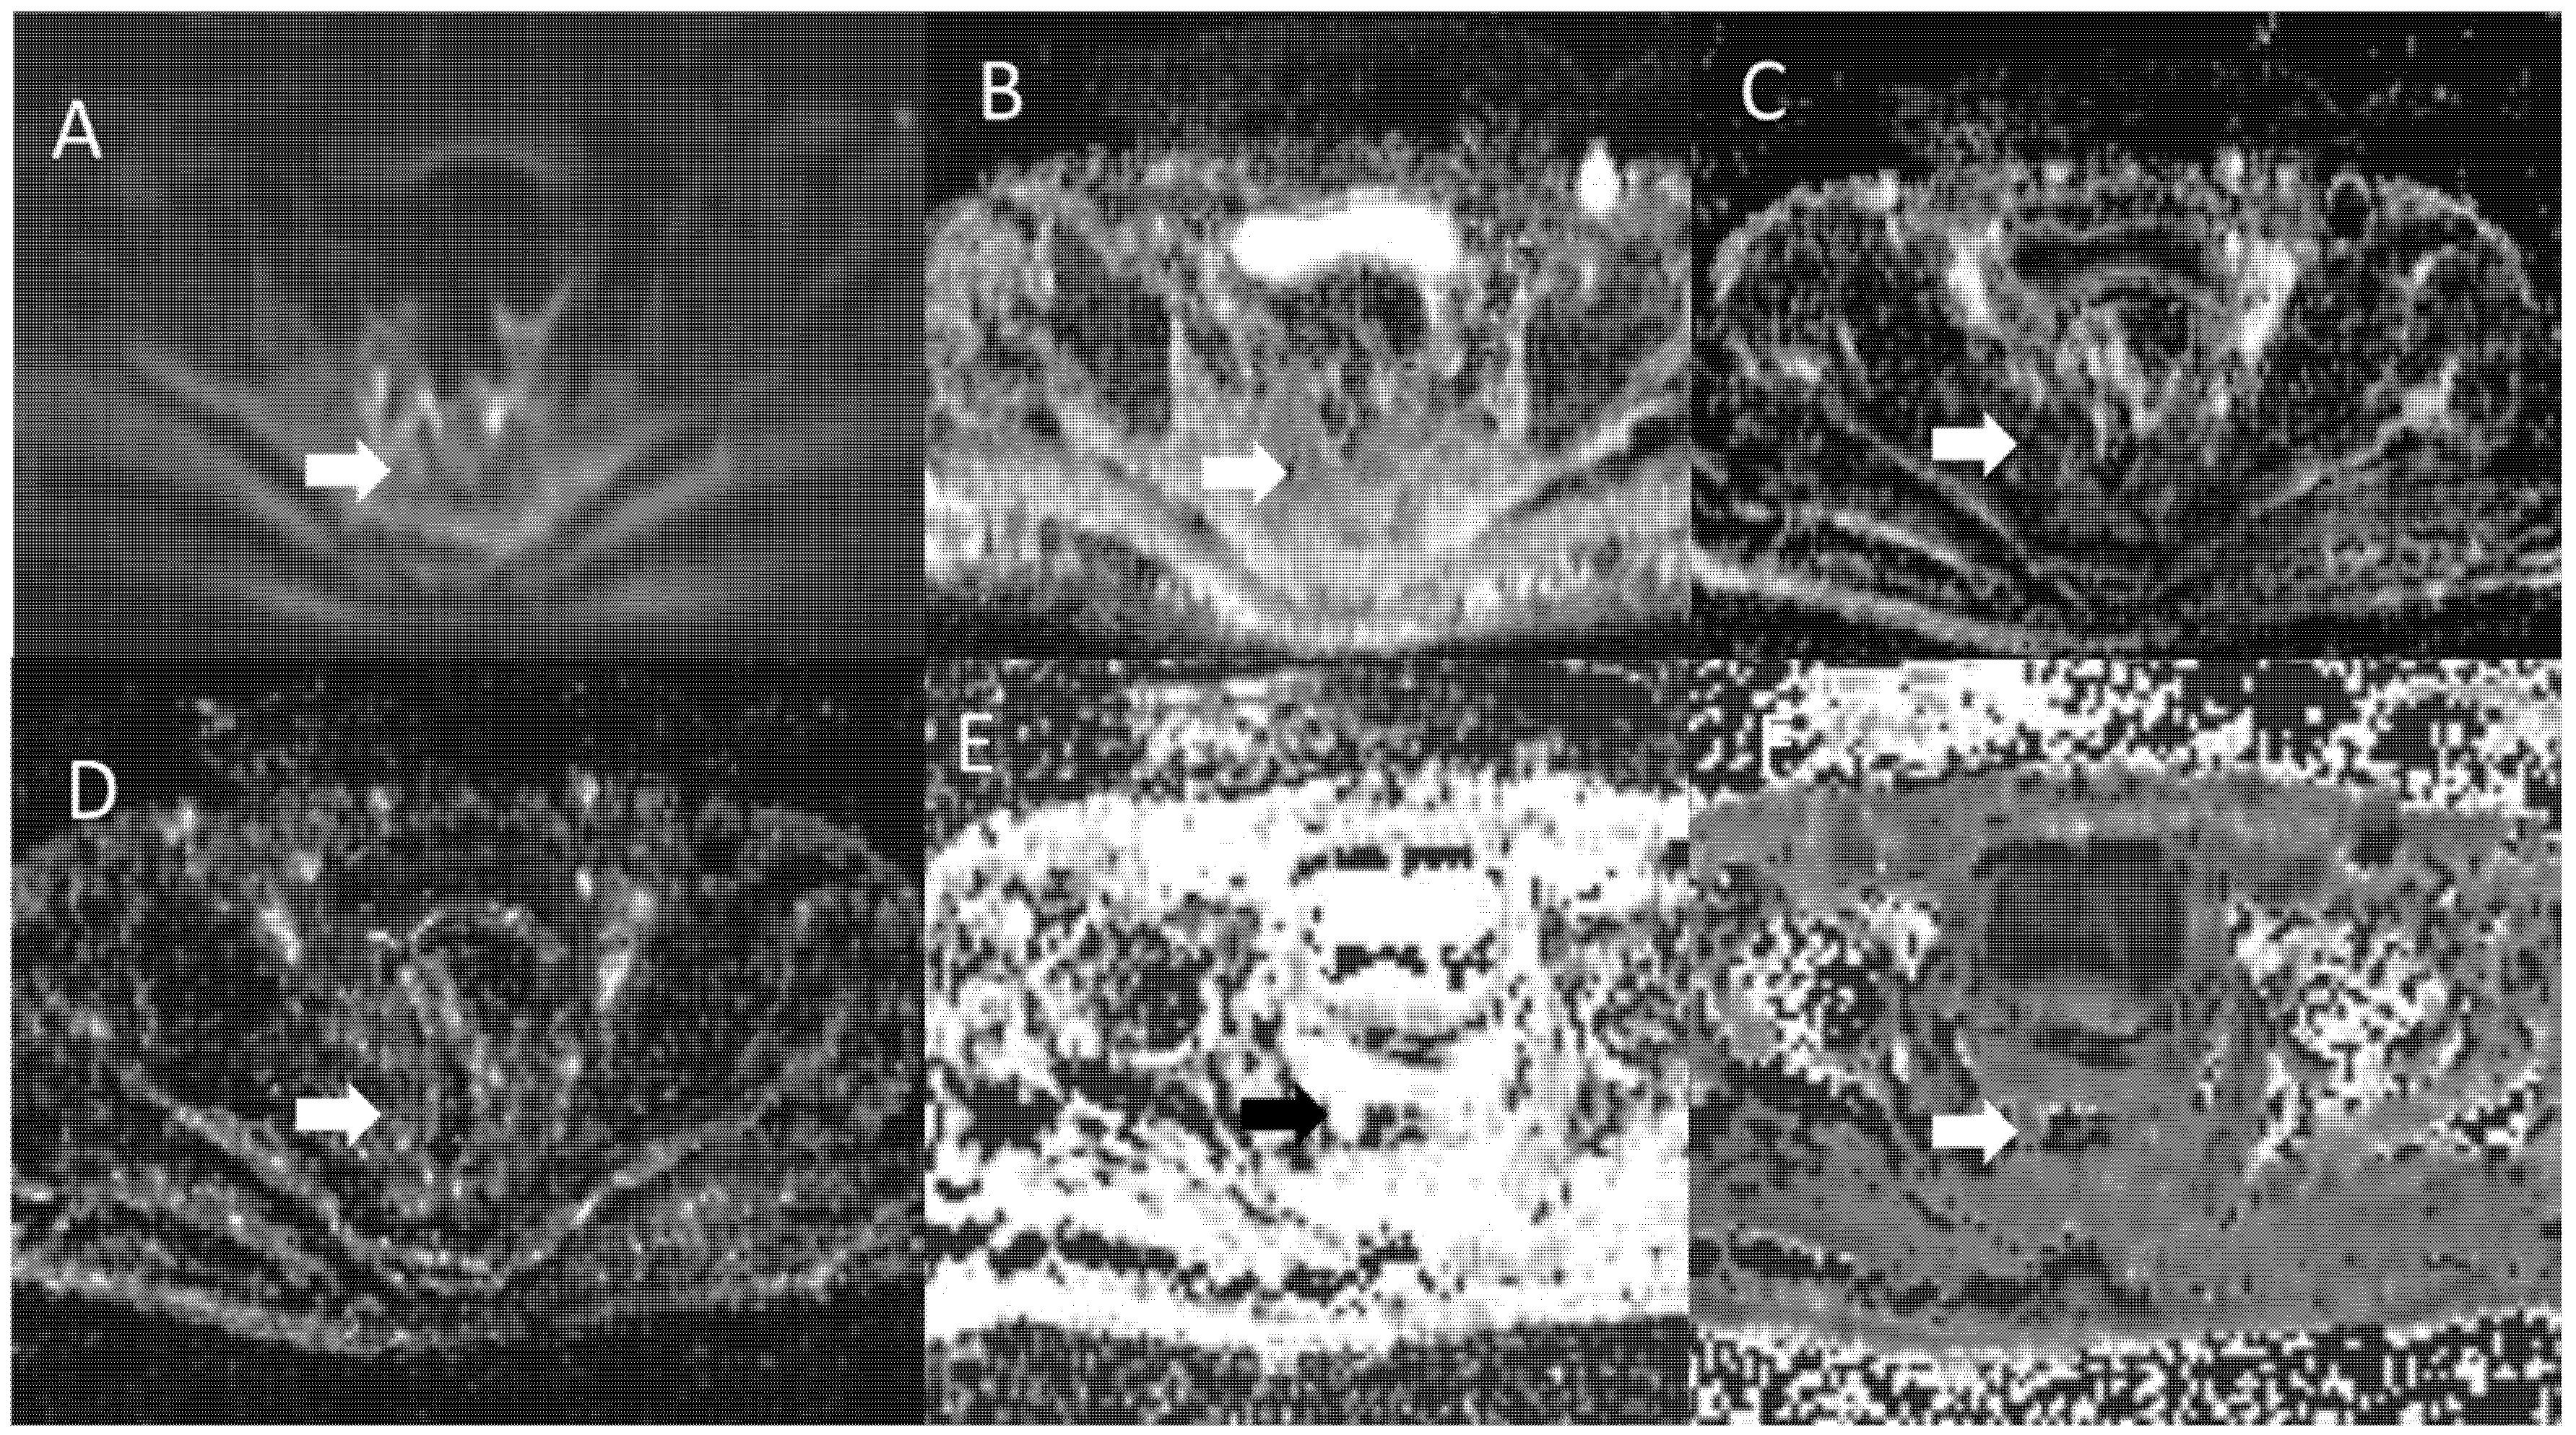

DWI Features